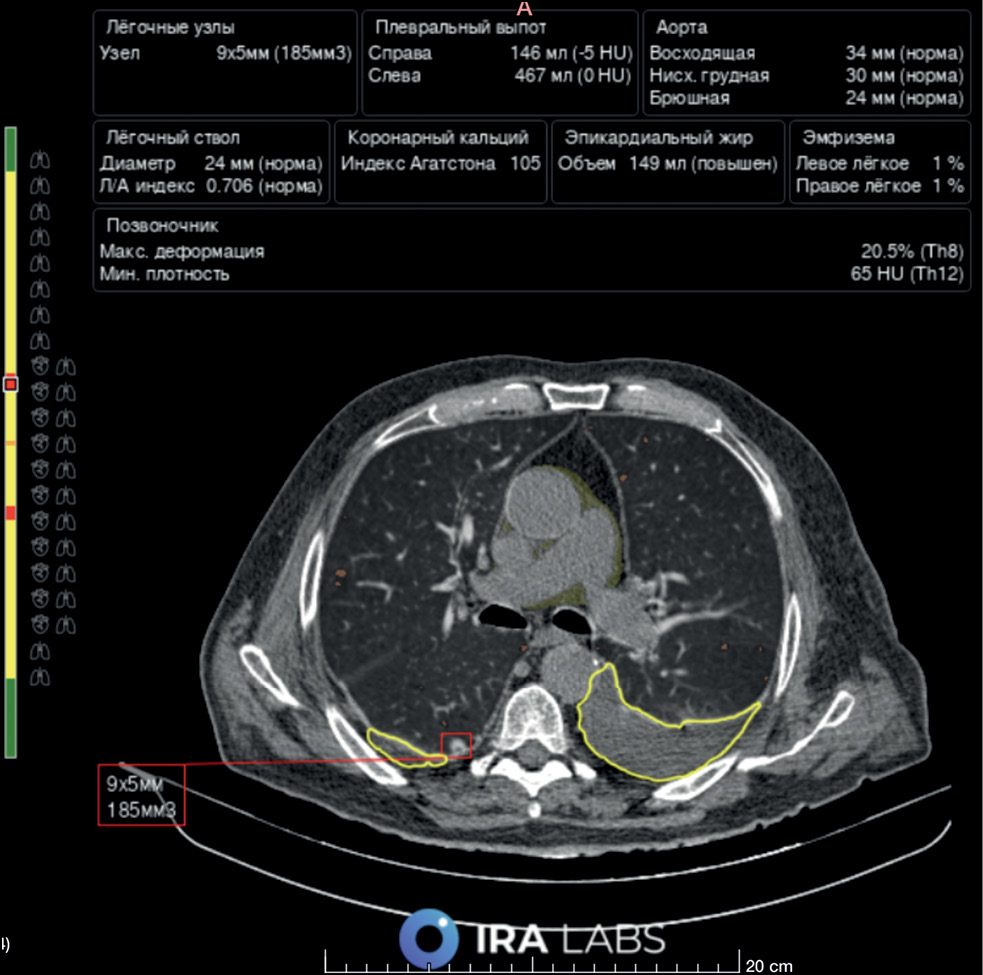

Fig. 6. An example of AI use. Patient B, 76 years old. A radiologist correctly identified bilateral hydrothorax and emphysematous changes but did not describe the lung nodule in the right lung. An AI algorithm revealed all three pathological findings: hydrothorax is highlighted with a yellow line, emphysematous changes are highlighted in orange, and the lung nodule is indicated by a red square.